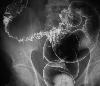

A case of multiple diverticulum and peridiverticular abscess of the sigmoid colon.

X-ray

Diverticulum/Diverticulitis, Peridiverticular Abscess